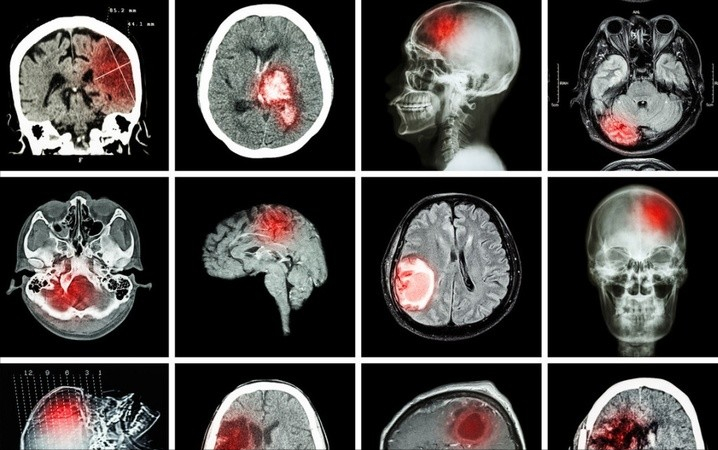

有这么一句话广为流传 , “一人得脑梗 , 全家要遭殃” 。 主要原因是脑梗几乎很难治愈 , 即便一开始治愈了也会导致许多后遗症 , 增加了无数家庭的压力 。

这也说明了脑梗的危害性十分严重 , 对我国国民的健康水平都造成了影响 。 所以 , 我们应该在平时就多多注意这件事 , 重视对心脑血管的保护 。

世界卫生组织研究成果表明:在我国每年脑梗患者会增加500多万 , 并且有200多万人因此而丧命 , 现在发病群体不限于高发于中老年人 , 脑梗也在逐步趋于年轻化 。